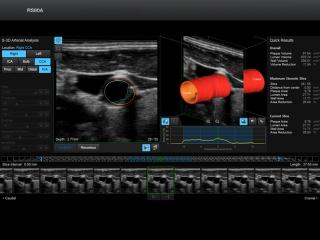

Common carotid artery, S-3D Arterial Analysis

RS80. Common carotid artery, S-3D Arterial Analysis.